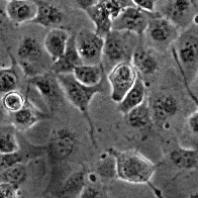

Паспорт клеточной линии CFTE 29o- из коллекции КККП ИНЦ РАН

Морфология:

эпителиоподобная

Способ культивирования:

монослойный